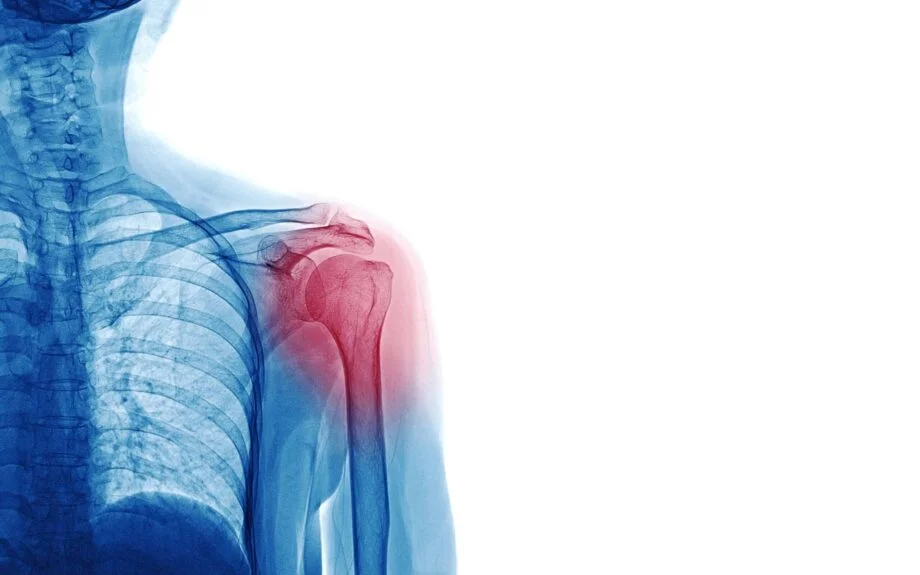

Understanding Shoulder Pain

The shoulders are complex structures made up of several joints combined with tendons and muscles that enable the shoulders to move with almost 360 degrees of motion. With more than a dozen muscles working together, our shoulders allow us to raise, twist, and move our arms. But when we injure a shoulder, the associated pain causes us to lose much of that range of motion.

Most shoulder problems are caused by inflamed or torn tendons, bursitis, rotator cuff injuries, osteoarthritis, or fractures. Rarely, the source of the pain can be tumors, infection, or nerve-related problems.